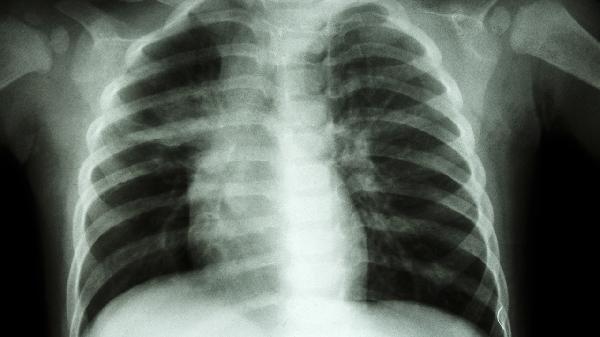

肺泡破裂导致气体进入胸膜腔时,突发刀割样胸痛伴随呼吸困难。瘦高体型青年自发性气胸概率较高,听诊患侧呼吸音减弱。X线检查可明确诊断,少量气胸可观察吸收,严重者需行胸腔闭式引流术。恢复期间禁止剧烈运动和乘坐飞机。